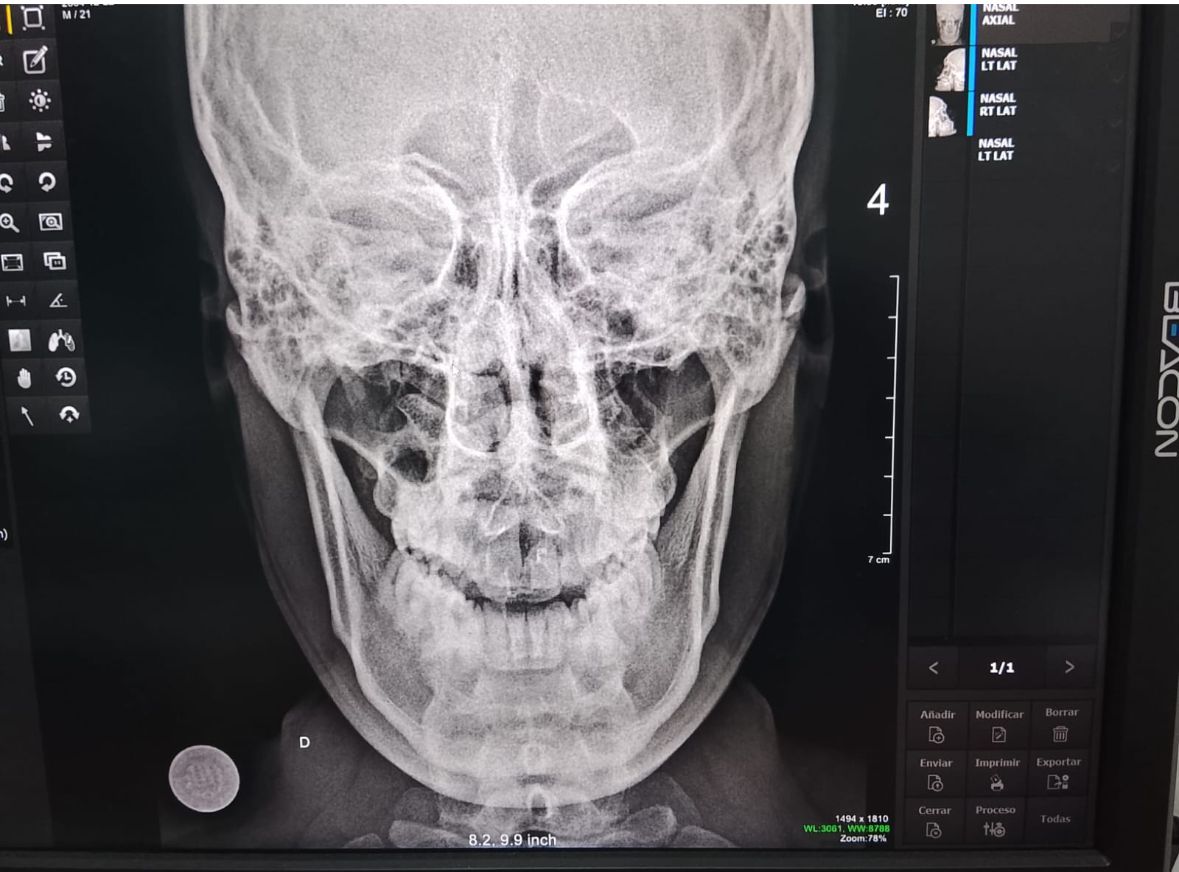

De acuerdo con la información disponible, el intervenido fue trasladado tras su detención; sin embargo, durante su permanencia en dicha dependencia habría protagonizado un violento ataque contra el suboficial de tercera Jean Pierre Reátegui Tafur, a quien presuntamente le propinó un rodillazo que le ocasionó la fractura del tabique.

El suboficial Reátegui Tafur permanece en proceso de recuperación debido a la lesión sufrida, la cual requeriría tratamiento especializado e inmovilización, lo que también afecta su capacidad de servicio en la institución policial.